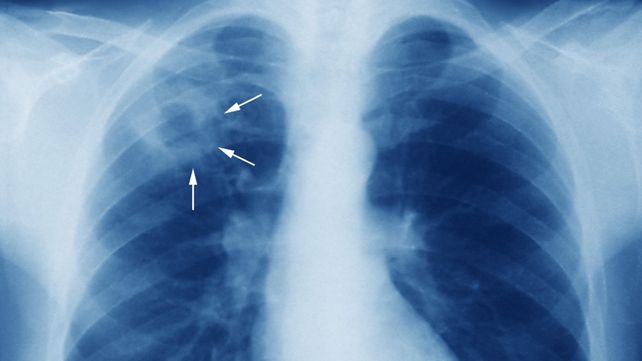

Tuberculosis: notificaciones a la baja en el panorama general

A diferencia de la sífilis, la notificación de casos totales de tuberculosis (TB) en Entre Ríos mostró una tendencia favorable en 2025 en comparación con el año anterior. Hasta la SE 44 de 2025, se notificaron 203 casos, lo que representa una tasa de 14 por 100.000 habitantes. Comparado con 2024 (247 casos y tasa de 17.2), se observó una variación porcentual negativa del -17.80%.

Sin embargo, en el análisis de tendencia a largo plazo en la población adolescente (15 a 19 años), Entre Ríos (ENR) registró una Variación Anual Promedio (VAP) de la tasa de notificación del 3.8% para el período 2021-2024, indicando una preocupación por el aumento sostenido en este grupo etario

Tuberculosis (TB)

TB en todas las edades:

• 2025: Se notificaron 203 casos de TB, con una tasa de 14 por 100.000 habitantes.

• 2024: Se notificaron 247 casos de TB, con una tasa de 17.2 por 100.000 habitantes.

• La variación porcentual de casos notificados entre 2024 y 2025 fue de -17.80% (descenso).

• En el año 2024, la tasa de notificación fue de 20.5 por 100.000 habitantes (294 casos).

TB en edad pediátrica y adolescente (Bienio 2023-2024):

• Edad pediátrica (0-14 años): La tasa fue de 3.3 por 100.000 habitantes (12 casos en 2023 / 10 casos en 2024).

• Adolescentes (15-19 años): La tasa fue de 15.3 por 100.000 habitantes (15 casos en 2023 / 18 casos en 2024).

• Para el grupo adolescente (15-19 años) en el período 2021-2024, Entre Ríos (ENR) registró una Variación Anual Promedio (VAP) de la tasa de notificación del 3.8%, lo que indica una tendencia al aumento.